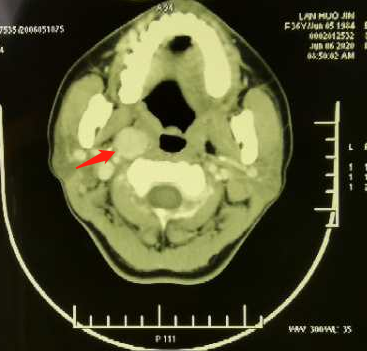

病例二

36岁年轻女性,发现颈前肿物半个月,诊断甲状腺癌双颈,右咽旁转移,咽旁转移淋巴结罕见,位于颈内动脉及静脉前方近颅底处,周围有重要的神经,一旦出血难以控制,手术难度大。

甲状腺癌一直被人们认为是“懒癌”,发展慢,效果好,但事实上并不都是,我院治疗过程中经常遇到晚期病人和多次术后复发难治的病人,这包括气管、喉侵犯、上纵隔转移等,对这些病人积极有效的治疗,延长病人的生存时间,也是头颈外科医生追求的目标。 手术团队术前详细分析影像资料,设计Macfee,s切口,兼顾甲状腺癌的根治与咽旁淋巴结清扫,同时在颈部入路无法切除肿瘤时可经口腔断下颌骨入路切除肿瘤,保证手术的安全,术中经颈部入路,将颈内动脉及静脉向上分离,离断二腹肌与茎突舌骨肌后显露右咽旁,完整清扫咽旁转移淋巴结。 上述两位疑难病例在切口设计、手术入路及修复方面充满挑战,但我院头颈外科迎难而上,充分发挥专科在疑难、晚期病例治疗上的优势,通过手术为主的综合治疗给病人带来长期控制癌肿的希望,获得长期生存机会。